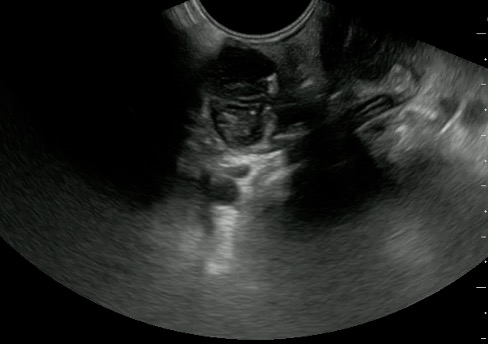

- Normal Tonsil

- The ovoid tonsils appear striated with hyperechoic bands and hypoechoic parenchyma, as well as lobulated margins.

- Figure 42 and 43. Normal Tonsil

Video 25. Normal tonsil